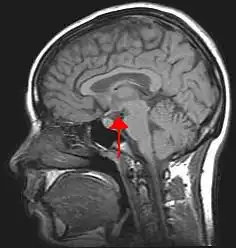

Location of the human hypothalamus | |

The hypothalamus (pl.: hypothalami; from Ancient Greek ὑπό (hupó) 'under' and θάλαμος (thálamos) 'chamber') is a small part of the vertebrate brain that contains a number of nuclei with a variety of functions. One of the most important functions is to link the nervous system to the endocrine system via the pituitary gland. The hypothalamus is located below the thalamus and is part of the limbic system.[1] It forms the basal part of the diencephalon. All vertebrate brains contain a hypothalamus.[2] In humans, it is about the size of an almond.[3]